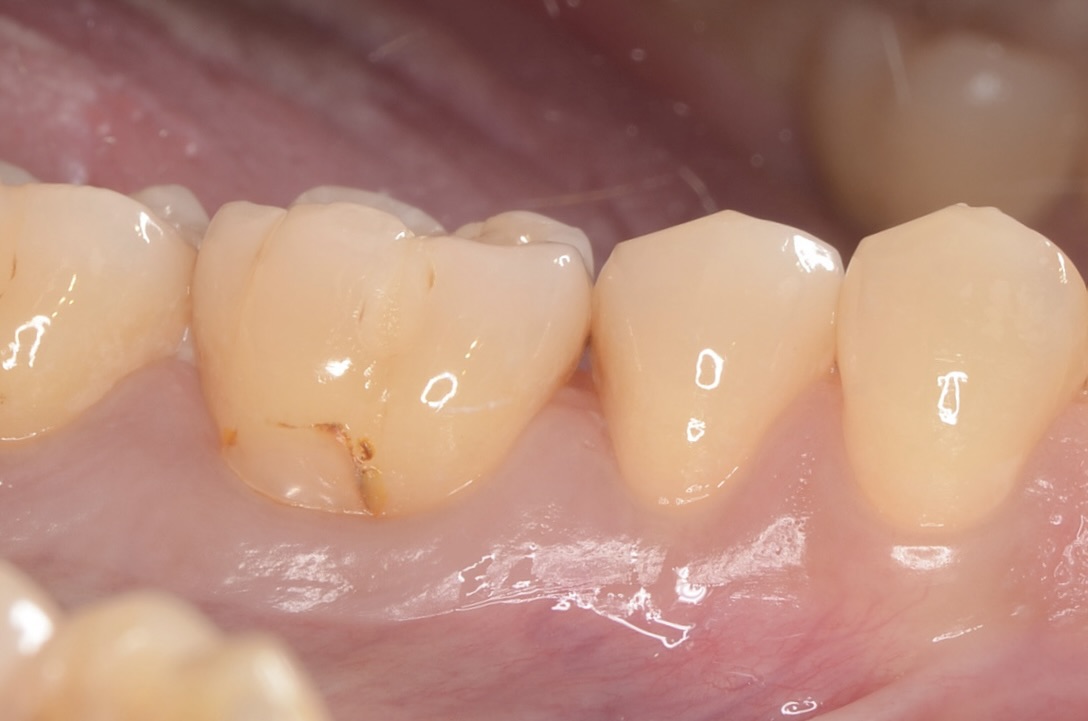

6番頬側の歯頸部

境目が茶色くなっている古いレジンがあります。 -

6番近心舌側の隣接面

茶色くなっている虫歯が見えます -